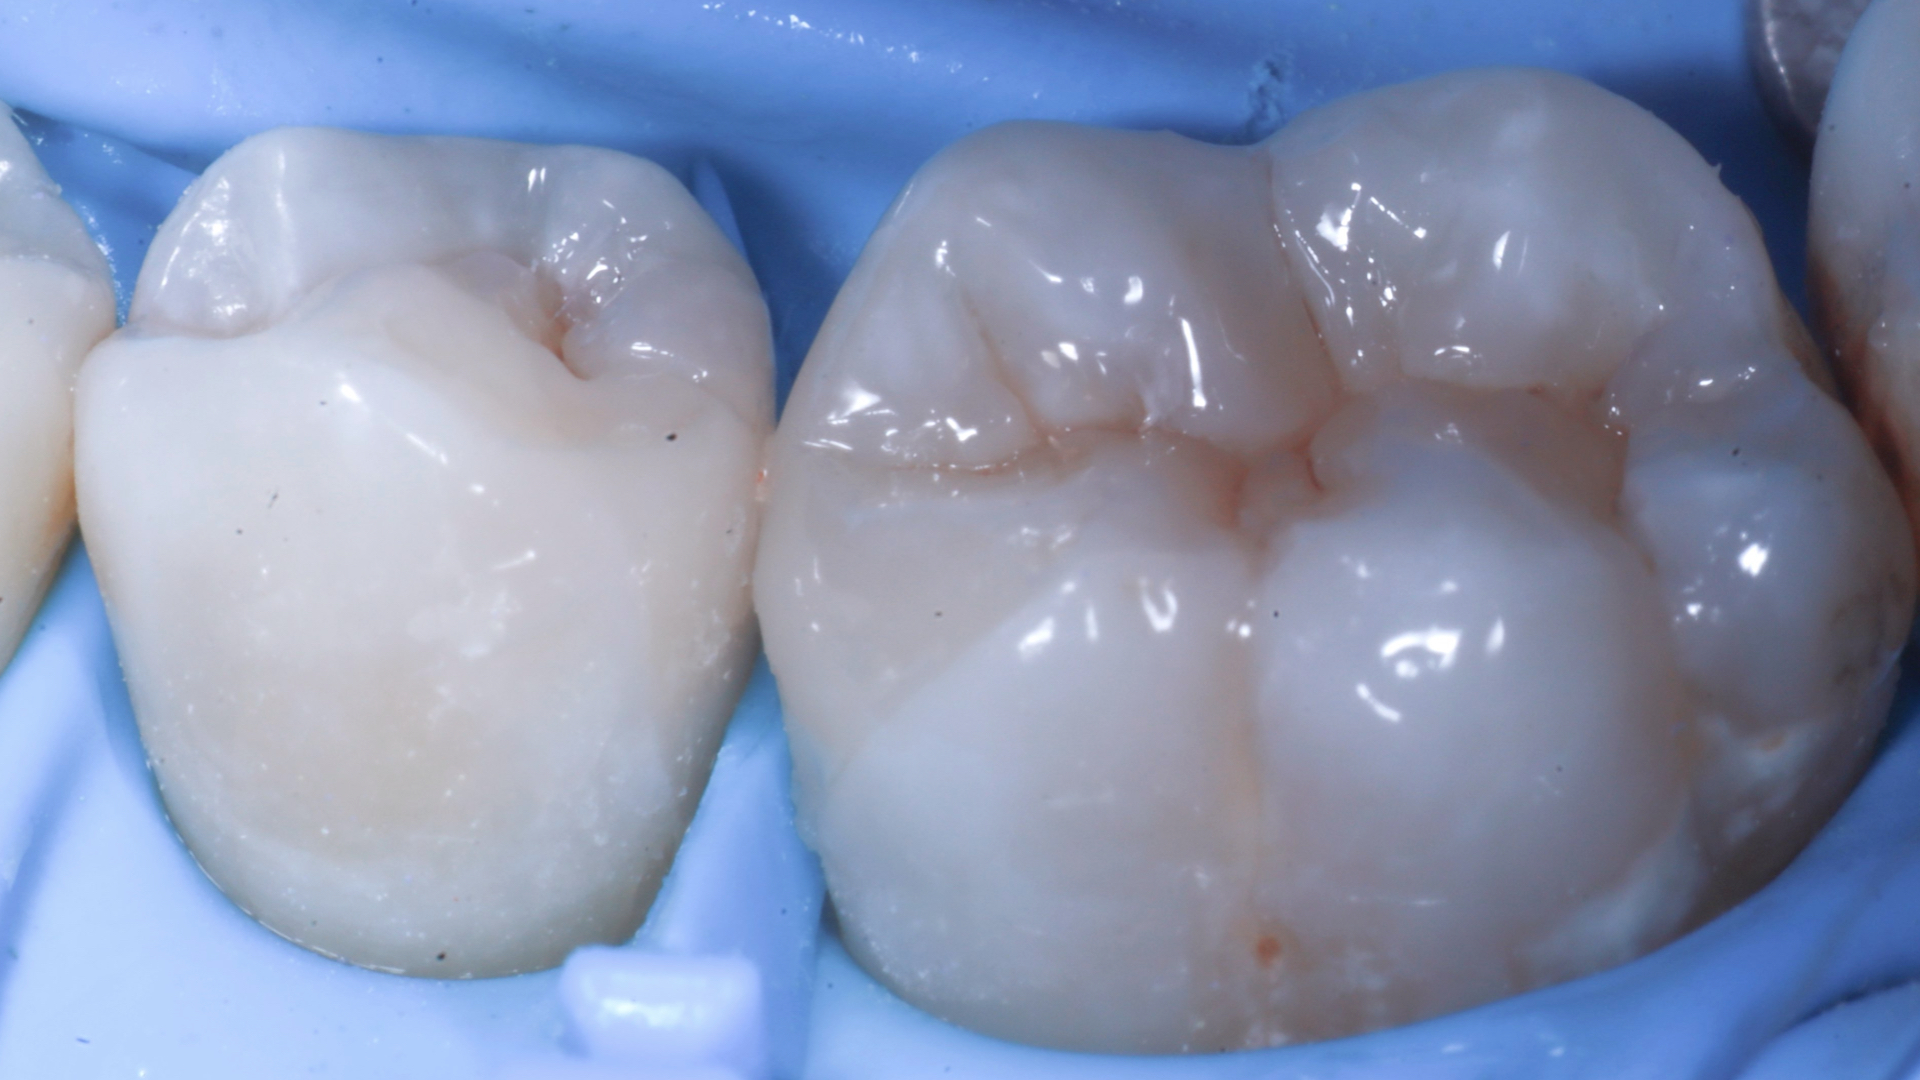

Isolamento con diga di gomma, creazione della cavità rimuovendo il vecchio restauro e la carie. Rifinitura della stessa cavità con frese diamantate a granulometria ridotta, strumenti reciprocanti e polveri a base di glicina Verifica fotografica del sigillo cervicale mesiale a 2.6